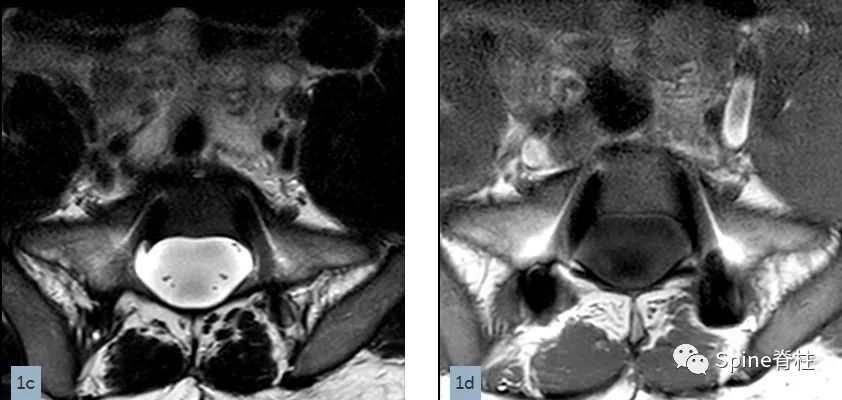

一名18岁男性因腰痛接受MRI检查,下图为矢状位T2(1a)和T1加权像(1b)、S1水平横断面T2(1c)和T1加权像(1d)。

在矢状位T2(2a)和T1加权像(2b)上,多节段椎体后壁呈扇形缺损,缺少硬膜外脂肪(红色箭头),S1处的硬膜囊直径大于L4处。横断面T2(2c)和T1加权像(2d)提示硬膜囊膨胀,S1椎体后壁再次证实硬膜外脂肪缺失(红色箭头)。 其影像学表现符合硬膜扩张的诊断